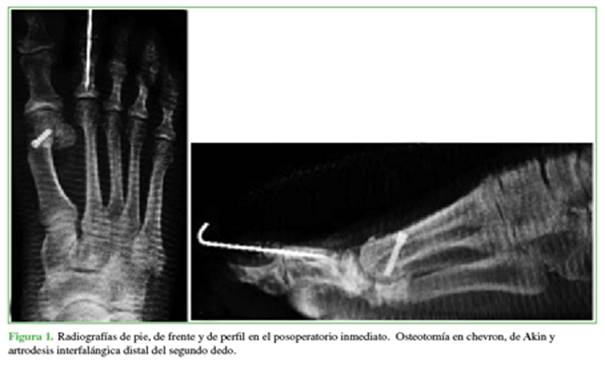

Se realizó un estudio retrospectivo, multicéntrico que incluyó a los pacientes sometidos a una osteotomía en chevron y de Akin (Figura 1) como tratamiento del hallux valgus leve o moderado, entre 2009 y 2018. Se evaluaron 1156 osteotomías en chevron en 1017 pacientes (355 bilaterales). El 95% eran mujeres y el 5% hombres, el rango etario era de 16 a 83 años (promedio 57.5). El procedimiento estuvo a cargo de cuatro cirujanos experimentados. Se realizó la osteotomía en V modificada por Johnson. La osteotomía se estabilizó con un tornillo de 3,0 mm con dirección de proximal a distal y de medial a lateral. A todos los pacientes se les tomaron radiografías en el posoperatorio inmediato, al mes, y a los tres y seis meses. Los pacientes con signos radiográficos de consolidación de la osteotomía fueron dados de alta a los seis meses de la cirugía.

De esta manera, la serie quedó conformada por cinco pacientes (4 del sexo femenino y 1 del sexo masculino) que contaban con estudios por imágenes compatibles con seudoartrosis a los seis meses de la operación (Figuras 2 y 3). Se empleó el puntaje de la escala de la AOFAS (American Orthopaedic Foot and Ankle Society) antes de ambos procedimientos (cirugía inicial del hallux valgus y cirugía de la seudoartrosis) y después.